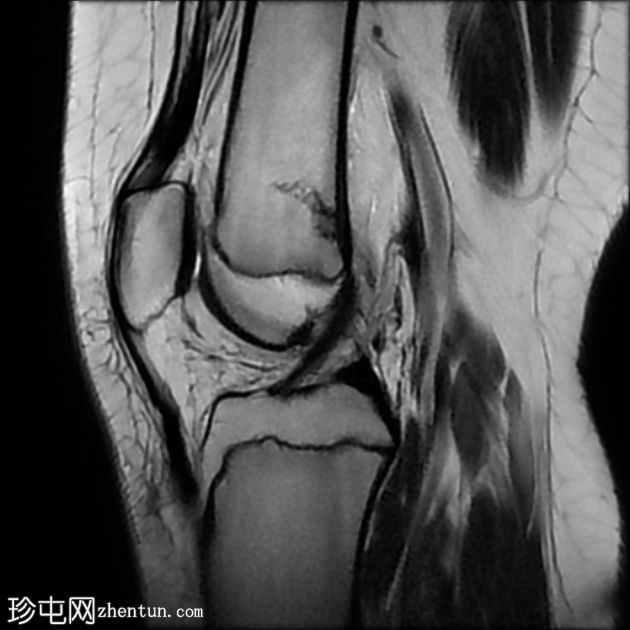

MRI

冠状位

STIR

股骨远端干骺端横向应力骨折线,在所有脉冲序列(T1、T2和STIR)上均呈低信号。其周围有骨髓水肿样信号。邻近骨膜软组织呈水肿样信号。

外侧半月板飞边。

髌腱止点增厚,信号增强,内侧有小部分撕裂。伴有胫骨结节突出和不规则,可能提示慢性Osgood-Schlatter病。

股骨干应力性损伤常见于中长跑运动员和新兵。

最初针对胫骨应力性损伤提出的MRI分级方案:

1级:骨膜水肿,无骨髓改变

2级:脂肪饱和T2加权像上可见骨髓水肿样信号

3级:T1加权像上也清晰可见骨髓水肿样信号

4级:T1和/或T2加权像上可见骨折线